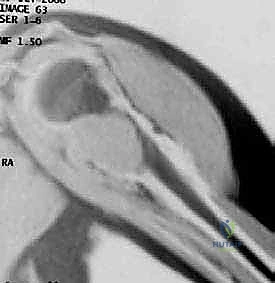

* MRI (T1-weighted, coronal): Invaluable for delineating the soft tissue extent of the tumor and its precise relationship to the neurovascular bundle. Crucially, it defines the intramedullary extent, especially vital for tumors like chondrosarcoma where plain radiographs can underestimate involvement.

Figure 3: Preoperative coronal T1-weighted MRI scan showing a lesion with intramedullary involvement.